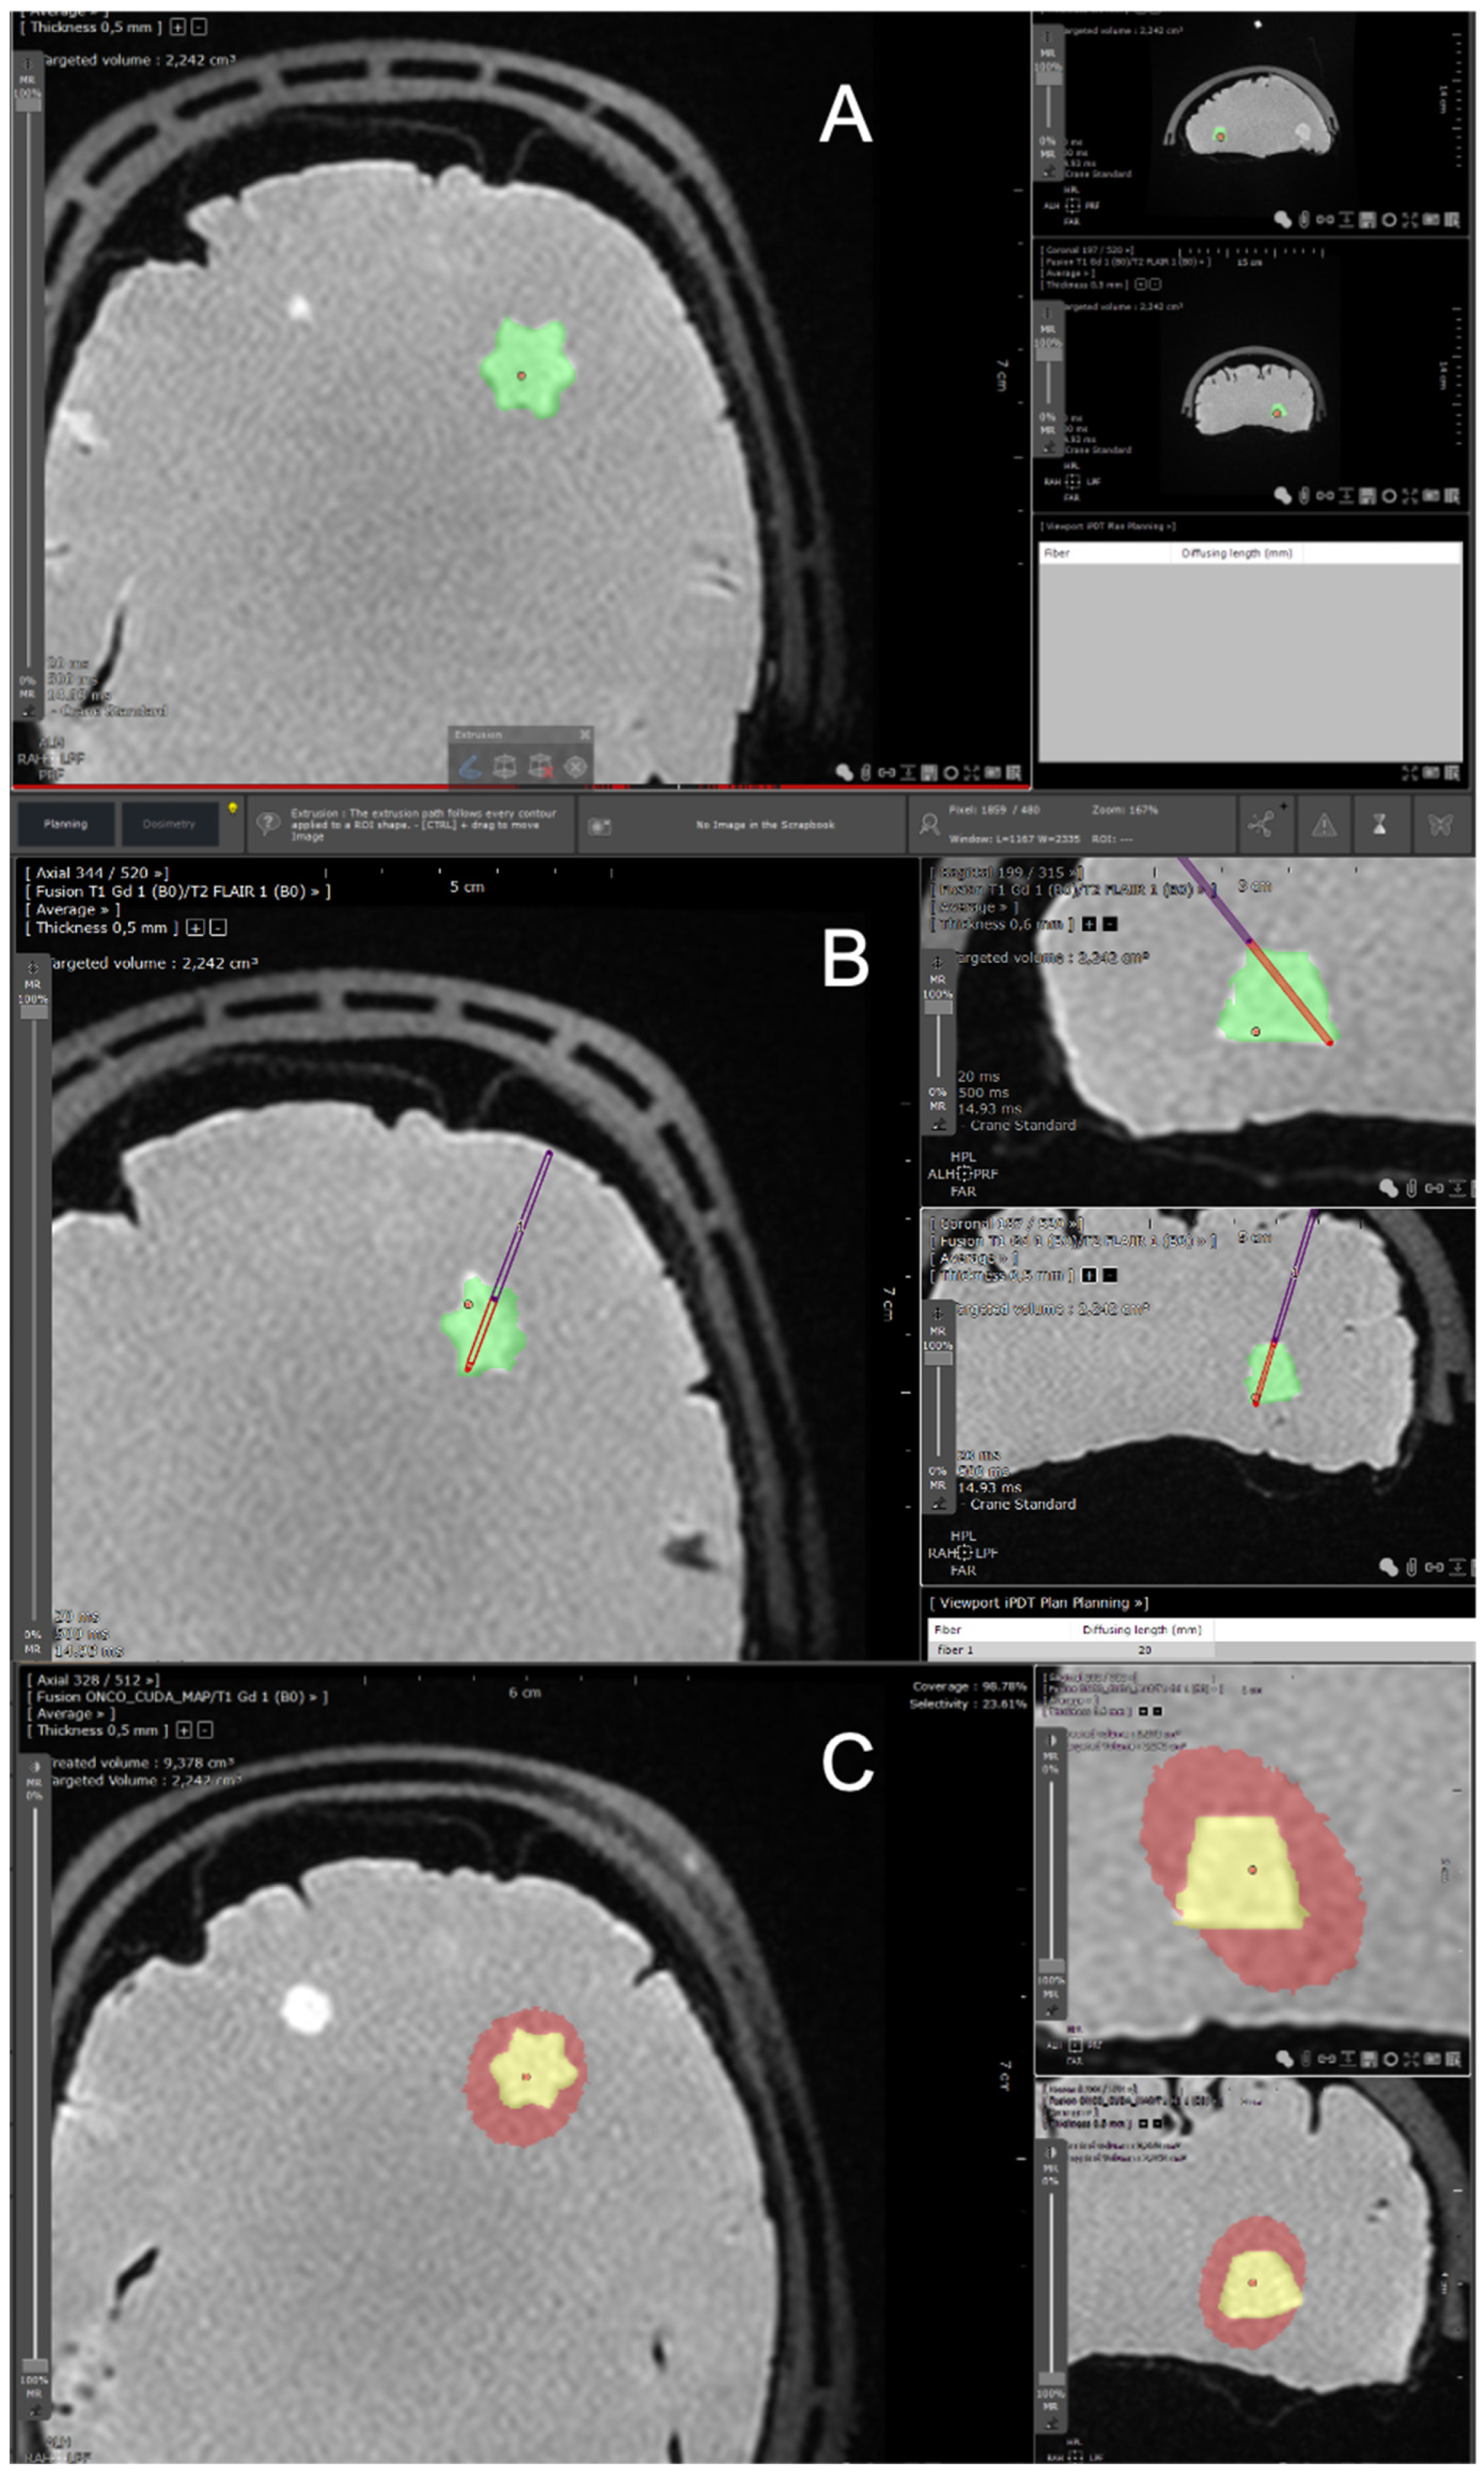

2.1. Planning Procedure

2.1.2. Segmentation Process

2.1.4. Optical Fibers Positioning

2.1.6. Monte Carlo Simulations

Definition of the Effective Treated Volume